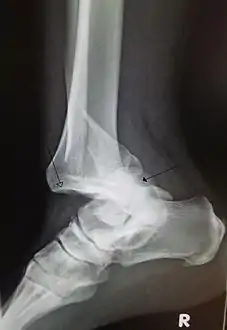

![]() انخلاع رضحى في المفصل الرصغى القصبى (tibiotarsal joint) للكعب مع كسر في عظمة الشظية بعيدا عن المفصل. السهم المفتوح يشير إلى عظمة القصبةبينما السهم المغلق يشير إلى عظم الكاحل. انخلاع رضحى في المفصل الرصغى القصبى (tibiotarsal joint) للكعب مع كسر في عظمة الشظية بعيدا عن المفصل. السهم المفتوح يشير إلى عظمة القصبةبينما السهم المغلق يشير إلى عظم الكاحل. | |